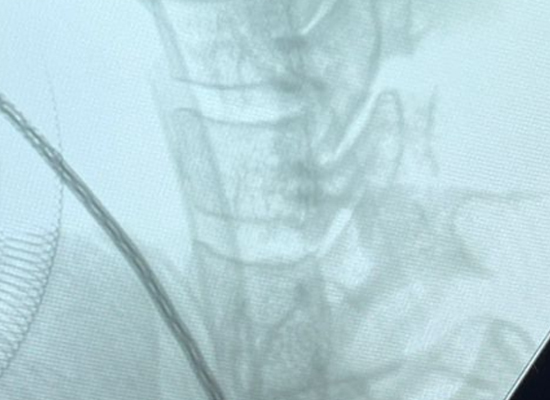

Intraoperative Imaging

Intraoperative view of Uni-C Standalone Cervical Cage placement during anterior cervical fusion by CZMEDITECH 1

Intraoperative view of Uni-C Standalone Cervical Cage placement during anterior cervical fusion by CZMEDITECH 2